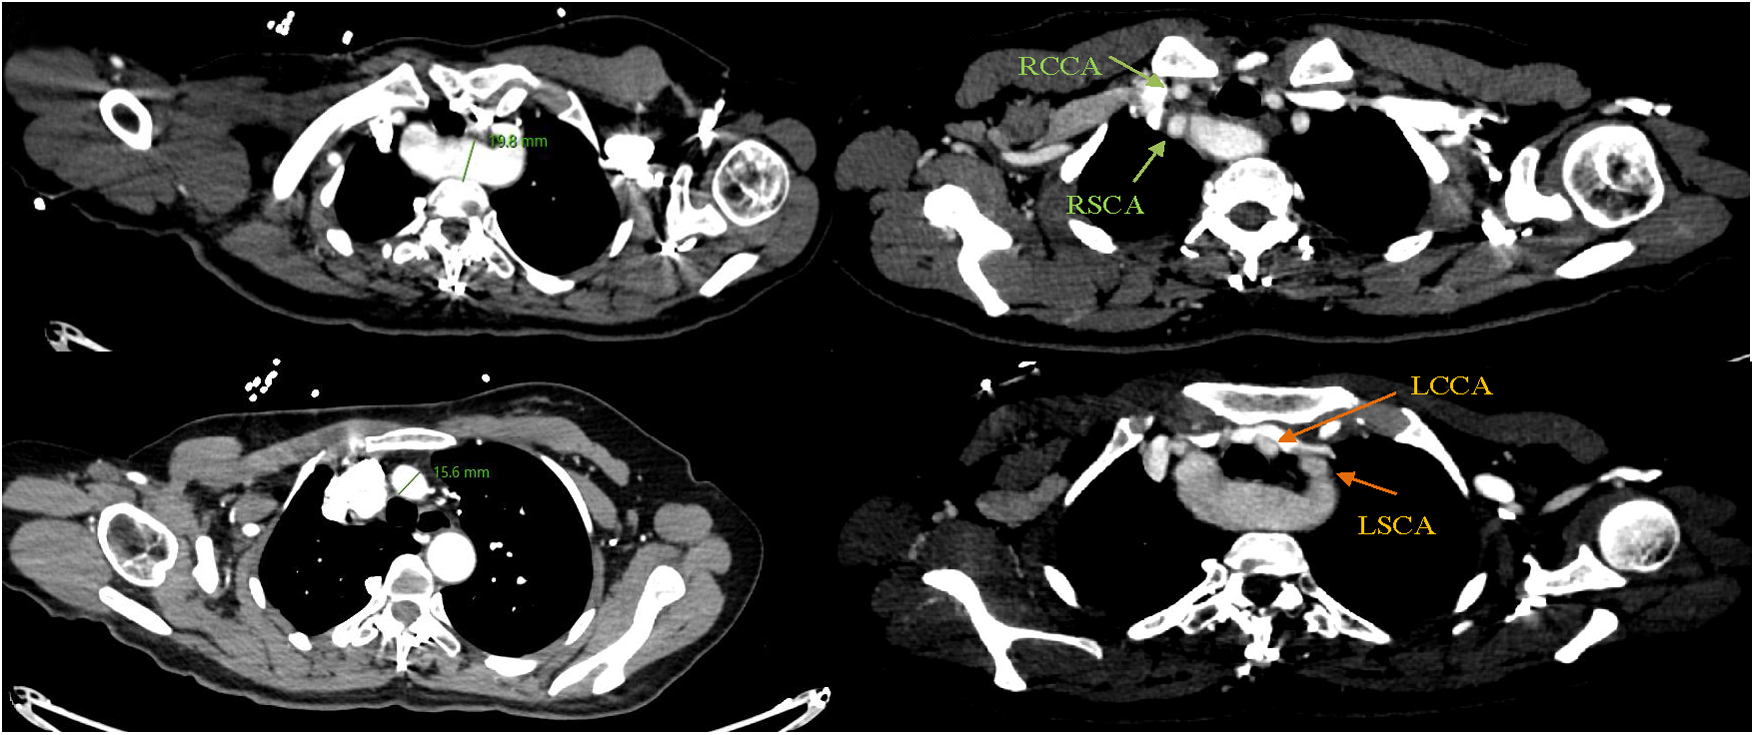

A 43-year-old female patient was admitted to the hospital due to recurrent chest and back pain for more than a month. CTA report indicated: aortic double arch malformation with dissection aneurysm in the descending aorta (Figure 1), right common carotid artery and right subclavian artery were originated from dominant right aortic arch, left subclavian artery and left common carotid artery were originated from left non-dominant left aortic arch (Figure 2).

Figure 1. CTA indicated that aortic double arch malformation with suspected development of dissection in the descending aorta.

Figure 2. Right common carotid artery (RCCA) and right subclavian artery (RSCA) were originated from dominant right aortic arch, left subclavian artery (LSCA) and left common carotid artery (LCCA) were originated from left non-dominant aortic arch.